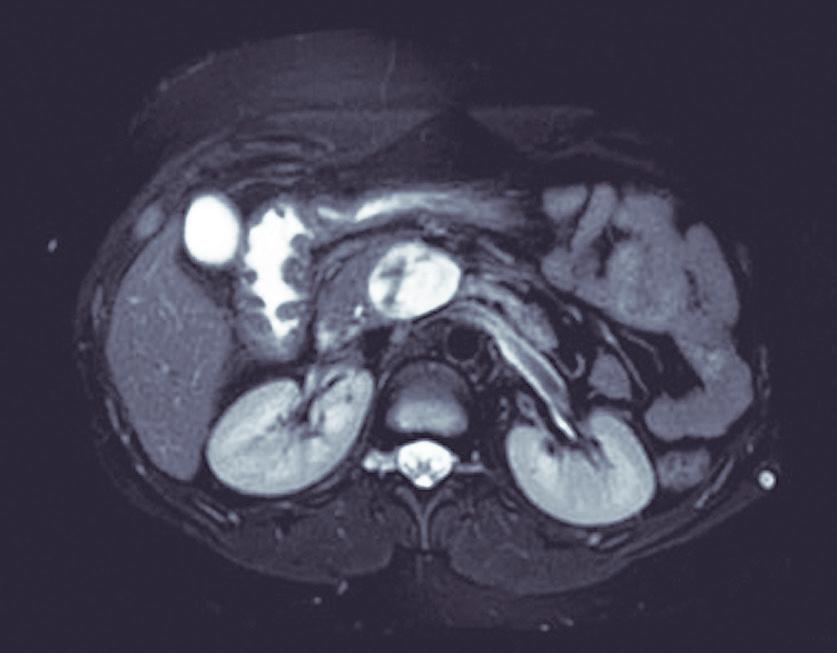

Neoplasia sólida pseudopapilar de páncreas: diagnóstico y manejo quirúrgico en una paciente joven

Elías Lessin García Alba, Magalí Chahdi Beltrame, Natalia Soledad Ruíz, Gabriel Cervantes, Marcelo Enrique Lenz Virreira, Francisco Juan Mattera, Emilio Gastón Quiñonez

Santiago Bustince, Nicolás H Dreifuss, Marcelo F Amante, Lucas McCormack, Pablo Capitanich

Pancreatic Atypical Neurofibromatous Neoplasm with Uncertain Biological Potential (ANNUBP) Mimicking a Solid Pseudopapillary Tumor Pancreatic ANNUBP